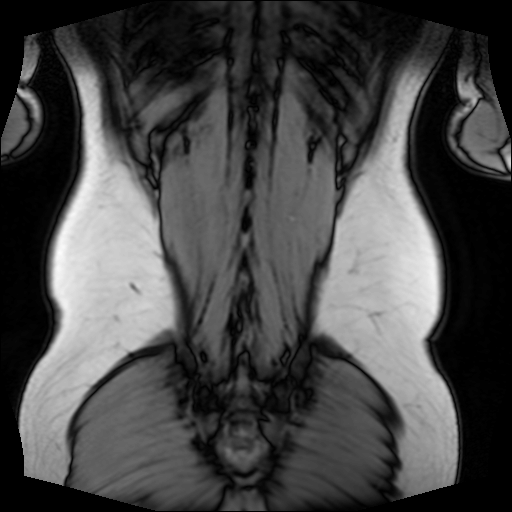

The following 512x512 image, for example, depicts my back, which is exported by the above script: